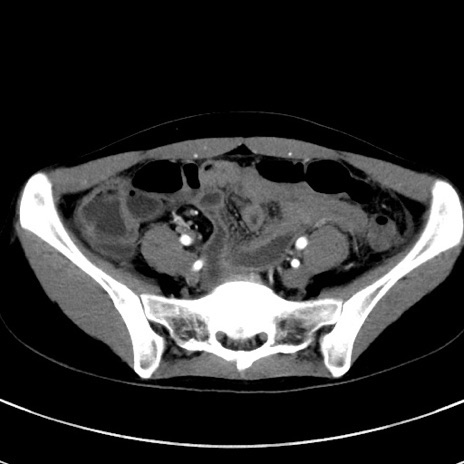

症例17(横断像)

【症例】20歳代女性

【主訴】嘔吐、下腹部痛

【現病歴】昨日夕食後に嘔吐し下腹部痛が出現。本日になっても嘔吐持続し改善しないため来院。

【身体所見】意識清明、BT 37.2℃、BP 108/67mmHg、腹部:平坦、やや硬、下腹部正中から右にかけて圧痛あり、反跳痛軽度あり、tapping pain(+)。

【データ】WBC 13600、CRP 14.94